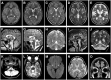

MED27 is a subunit of the Mediator multiprotein complex, which is involved in transcriptional regulation. Biallelic MED27 variants have recently been suggested to be responsible for an autosomal recessive neurodevelopmental disorder with spasticity, cataracts and cerebellar hypoplasia. We further delineate the clinical phenotype of MED27-related disease by characterizing the clinical and radiological features of 57 affected individuals from 30 unrelated families with biallelic MED27 variants. Using exome sequencing and extensive international genetic data sharing, 39 unpublished affected individuals from 18 independent families with biallelic missense variants in MED27 have been identified (29 females, mean age at last follow-up 17 ± 12.4 years, range 0.1-45). Follow-up and hitherto unreported clinical features were obtained from the published 12 families. Brain MRI scans from 34 cases were reviewed. MED27-related disease manifests as a broad phenotypic continuum ranging from developmental and epileptic-dyskinetic encephalopathy to variable neurodevelopmental disorder with movement abnormalities. It is characterized by mild to profound global developmental delay/intellectual disability (100%), bilateral cataracts (89%), infantile hypotonia (74%), microcephaly (62%), gait ataxia (63%), dystonia (61%), variably combined with epilepsy (50%), limb spasticity (51%), facial dysmorphism (38%) and death before reaching adulthood (16%). Brain MRI revealed cerebellar atrophy (100%), white matter volume loss (76.4%), pontine hypoplasia (47.2%) and basal ganglia atrophy with signal alterations (44.4%). Previously unreported 39 affected individuals had seven homozygous pathogenic missense MED27 variants, five of which were recurrent. An emerging genotype-phenotype correlation was observed. This study provides a comprehensive clinical-radiological description of MED27-related disease, establishes genotype-phenotype and clinical-radiological correlations and suggests a differential diagnosis with syndromes of cerebello-lental neurodegeneration and other subtypes of 'neuro-MEDopathies'.